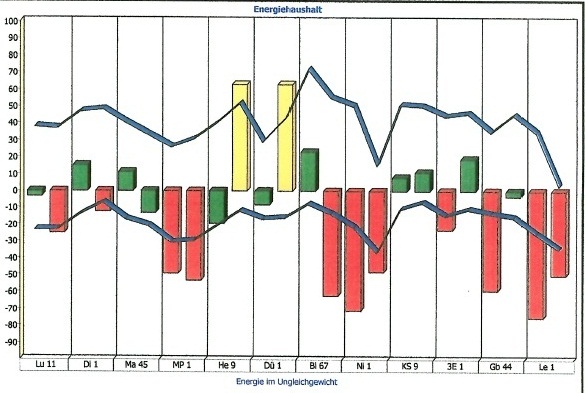

Nachfolgend Ergebnisse einer Studie, die über die Messung des menschlichen Meridiansystems aus der Traditionellen Chinesischen Medizin durchgeführt wurde, vor und nach der Betrachtung von Elementarkunst.

Steigt Energie,

entsteht Kreativität.

Sinkt Energie,

entsteht Arbeit.

Sie können unter Fakten, Ergebnisse aus meiner Studie über die Wirkung der Initiativbilder einsehen, unter "Indirekt" Person 1 und 2 vorher und nachher.